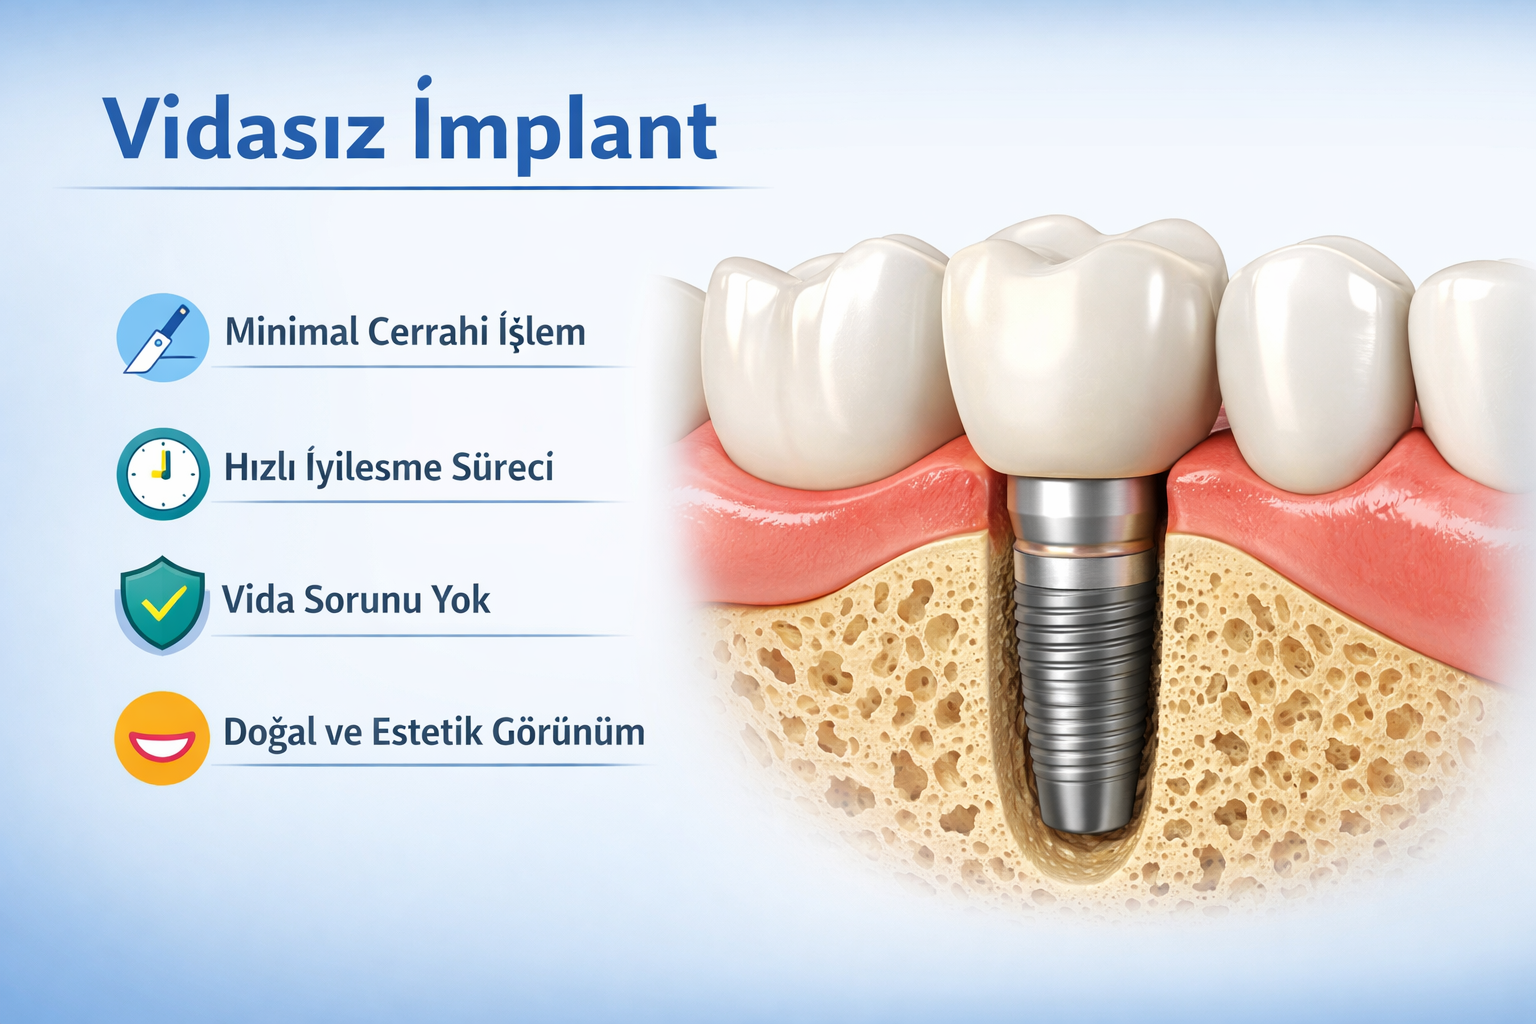

Vidasız İmplant Nedir?

Vidasız implant; titanyumdan üretilen, yüzeyi özel olarak tasarlanmış ve çene kemiğine vidalanmadan sabitlenen bir implant sistemidir. İmplantın yüzey yapısı ve formu, kemiğe sıkı şekilde tutunmasını sağlayacak biçimde geliştirilmiştir.

Vidalı implantlardan farkı, implantın kemiğe vida ile değil, press-fit (sıkıştırma) yöntemiyle yerleştirilmesidir. Bu sayede daha az cerrahi işlem uygulanır ve iyileşme süreci çoğu vakada daha konforlu ilerler.

Daha Az Cerrahi Müdahale

Vidasız implant sistemleri, vidalı implantlara göre daha minimal cerrahi işlem gerektirir. Vida yuvası açılmadığı için işlem süresi kısalır ve doku travması azalır.

Daha Hızlı İyileşme Süreci

Cerrahi işlemin daha basit olması sayesinde, hastalar çoğu zaman daha az ağrı, daha az şişlik ve daha kısa iyileşme süresi yaşar.

Vida Kaynaklı Sorunlar Ortadan Kalkar

Estetik Açıdan Üstünlük Sağlar

Özellikle ön diş implantı uygulamalarında vidasız implantlar daha doğal bir görünüm sunar. Vida deliği kapatma ihtiyacı olmadığı için porselen dişlerde estetik sorun oluşma riski azalır.